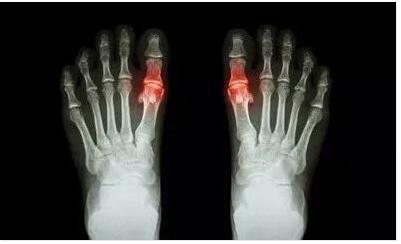

痛风是嘌呤代谢紊乱及(或)尿酸排泄减少而致尿酸盐沉积引起的一种 ...

脚疼痛风的症状是什么?脚疼痛风给患者带来了很大的伤害,让患者 ...